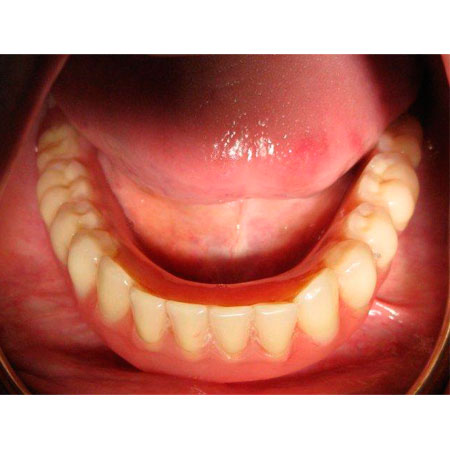

Nº3 DENTADURA COMPLETA ESTABILIZADA CON IMPLANTES

Una periodontitis muy avanzada hizo recomendable la extracción de todos los dientes y la rehabilitación de toda la dentadura mediante implantes y prótesis cerámica.